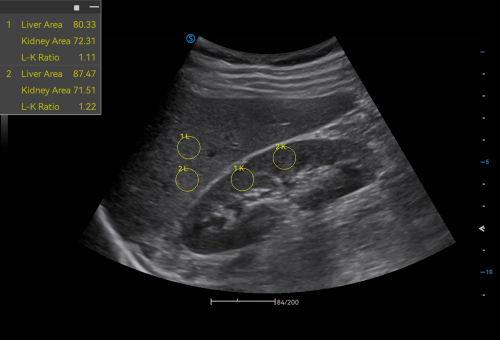

Click on images to enlarge

Intelligent Breast Solutions on the Workstation

Automatic lesion detection powered by AI identifies suspected area and traces the lesion from multiple sections. Quantitative coordinate position and graphic indication will be displayed for precise lesion localization.